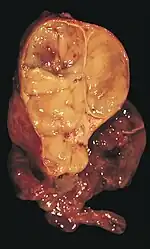

Les thymomes se présentent comme une masse bien définie du médiastin antérieur, proche du péricarde et dans un plan plus antérieur que les gros vaisseaux intrathoraciques (aorte ascendante et sa crosse, artère pulmonaire, veine cave supérieure). La masse peut être sphérique ou lobulée, mais présente un aspect homogène (plus rarement kystique) qui se réhausse après injection et peut contenir des calcifications[29].

Les critères scanographiques d'envahissement local doivent être recherchés car ils guideront le traitement. D'autre part, l'envahissement scanographique est corrélé au pronostic[30]. L'absence d'un liseré graisseux entre la masse et les vaisseaux, notamment l'aorte et la veine cave supérieure, est un signe d'envahissement local. L'ascension d'une coupole diaphragmatique, comme en radiographie thoracique, est un signe d'envahissement du nerf phrénique[31].

L'irrégularité des contours de la tumeur, ainsi que la présence de calcifications, de nécrose ou d'hémorragie intratumorale sont des signes de mauvais pronostic corrélés à des tumeurs plus agressives[32].